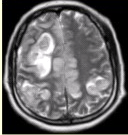

- [材料题] 女性,产后癫痫、剧烈头痛1天,意识障碍3小时。MRI显示如下图。

- 多项选择题1.关于MRI表现的描述,正确的是

A、双侧额叶、顶叶皮质肿胀,脑沟变浅

B、病变同时累及皮质及皮质下白质

C、上矢状窦流空信号消失

D、病变占位效应明显

E、病变信号均匀

F、病变邻近脑膜增厚